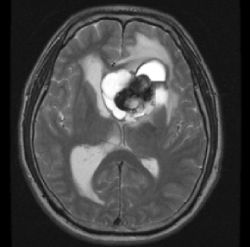

Эпендимома — это редко встречающийся тип опухоли центральной нервной системы. Новообразование формируется в головном мозге (его желудочковой системе) или в спинном мозге. Болезнь может развиться как у взрослых, так и у детей. Основной метод лечения — хирургическое удаление эпендимомы.

Опухоль образуется из клеток эпендимы — тонкого слоя, выстилающего внутреннее пространство желудочков головного мозга и центрального спинномозгового канала. Новообразование может иметь как доброкачественный, так и злокачественный характер. Внутричерепные неоплазии бывают злокачественными чаще, чем спинальные.

В головном мозге эпендимомы преимущественно располагаются в задней черепной ямке, в области четвёртого мозгового желудочка. При такой локализации опухоль может оказывать давление на мозжечок, ствол мозга. Из-за разрастания тканей нередко нарушается динамика движения ликвора — жидкости, омывающей головной и спинной мозг. При злокачественной форме неоплазия может прорастать в окружающие нервные ткани, в мозжечок. Эпендимомы у детей в большинстве случаев бывают внутричерепными.

- МРТ либо КТ головного, спинного мозга;

Чтобы оценить распространённость неоплазии, врач выполняет люмбальную пункцию и цитологическое исследование ликвора. Окончательно классифицировать опухоль позволяет микроскопическое изучение её тканей, полученных в процессе операции или при помощи биопсии.

Основной метод лечения эпендимомы — хирургический. Врач выполняет полное удаление опухоли. Для повышения точности и безопасности нейрохирургического вмешательства применяются нейронавигационные системы. Наиболее сложным для манипуляций является расположение неоплазии в черепной ямке. Если радикальное удаление невозможно, операция дополняется лучевой терапией или химиотерапией. Для восстановления нормальной циркуляции ликвора может быть выполнено шунтирование.